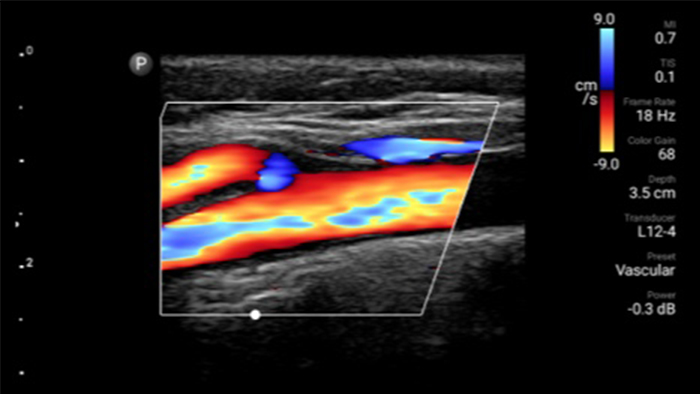

Lumify L12-4 broadband linear array transducer

• 4 to 1 MHz extended operating frequency range • 2D, color Doppler, M-mode, advanced XRES and multivariate harmonic imaging • High-resolution imaging for abdominal and cardiac applications: Cardiac, OB/GYN, Lung, Abdomen and FAST imaging preset optimizations